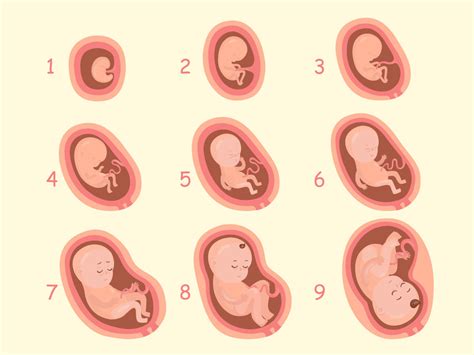

Na prvem ultrazvočnem pregledu se ocenjuje prisotnost, velikost in oblika gestacijske vrečke (ali več vrečk), prisotnost in velikost rumenjaka ter velikost ploda. V 4. tednu nosečnosti je gestacijska vrečka najzgodnejši ultrazvočni prikaz nosečnosti. Rumenjak postane viden v 5. tednu, srčna aktivnost ploda pa se pogosto zazna že pred oblikovanjem plodove celice. Plod od 6. tedna naprej raste približno 1 mm na dan. Dolžina ploda od glave do trtice (CRL) je najbolj natančno merilo gestacijske starosti v zgodnji nosečnosti.

V prvih tednih nosečnosti lahko zaradi zgodnejše ali poznejše oploditve ali ugnezditve zarodka opazimo različne slike, ki se lahko razlikujejo za nekaj dni. Meritev nuhalne svetline se opravi med 11. in 14. tednom, medtem ko se morfološki pregled ploda opravi med 20. in 24. tednom. Četrti ultrazvok pa običajno sledi med 32. in 34. tednom nosečnosti.